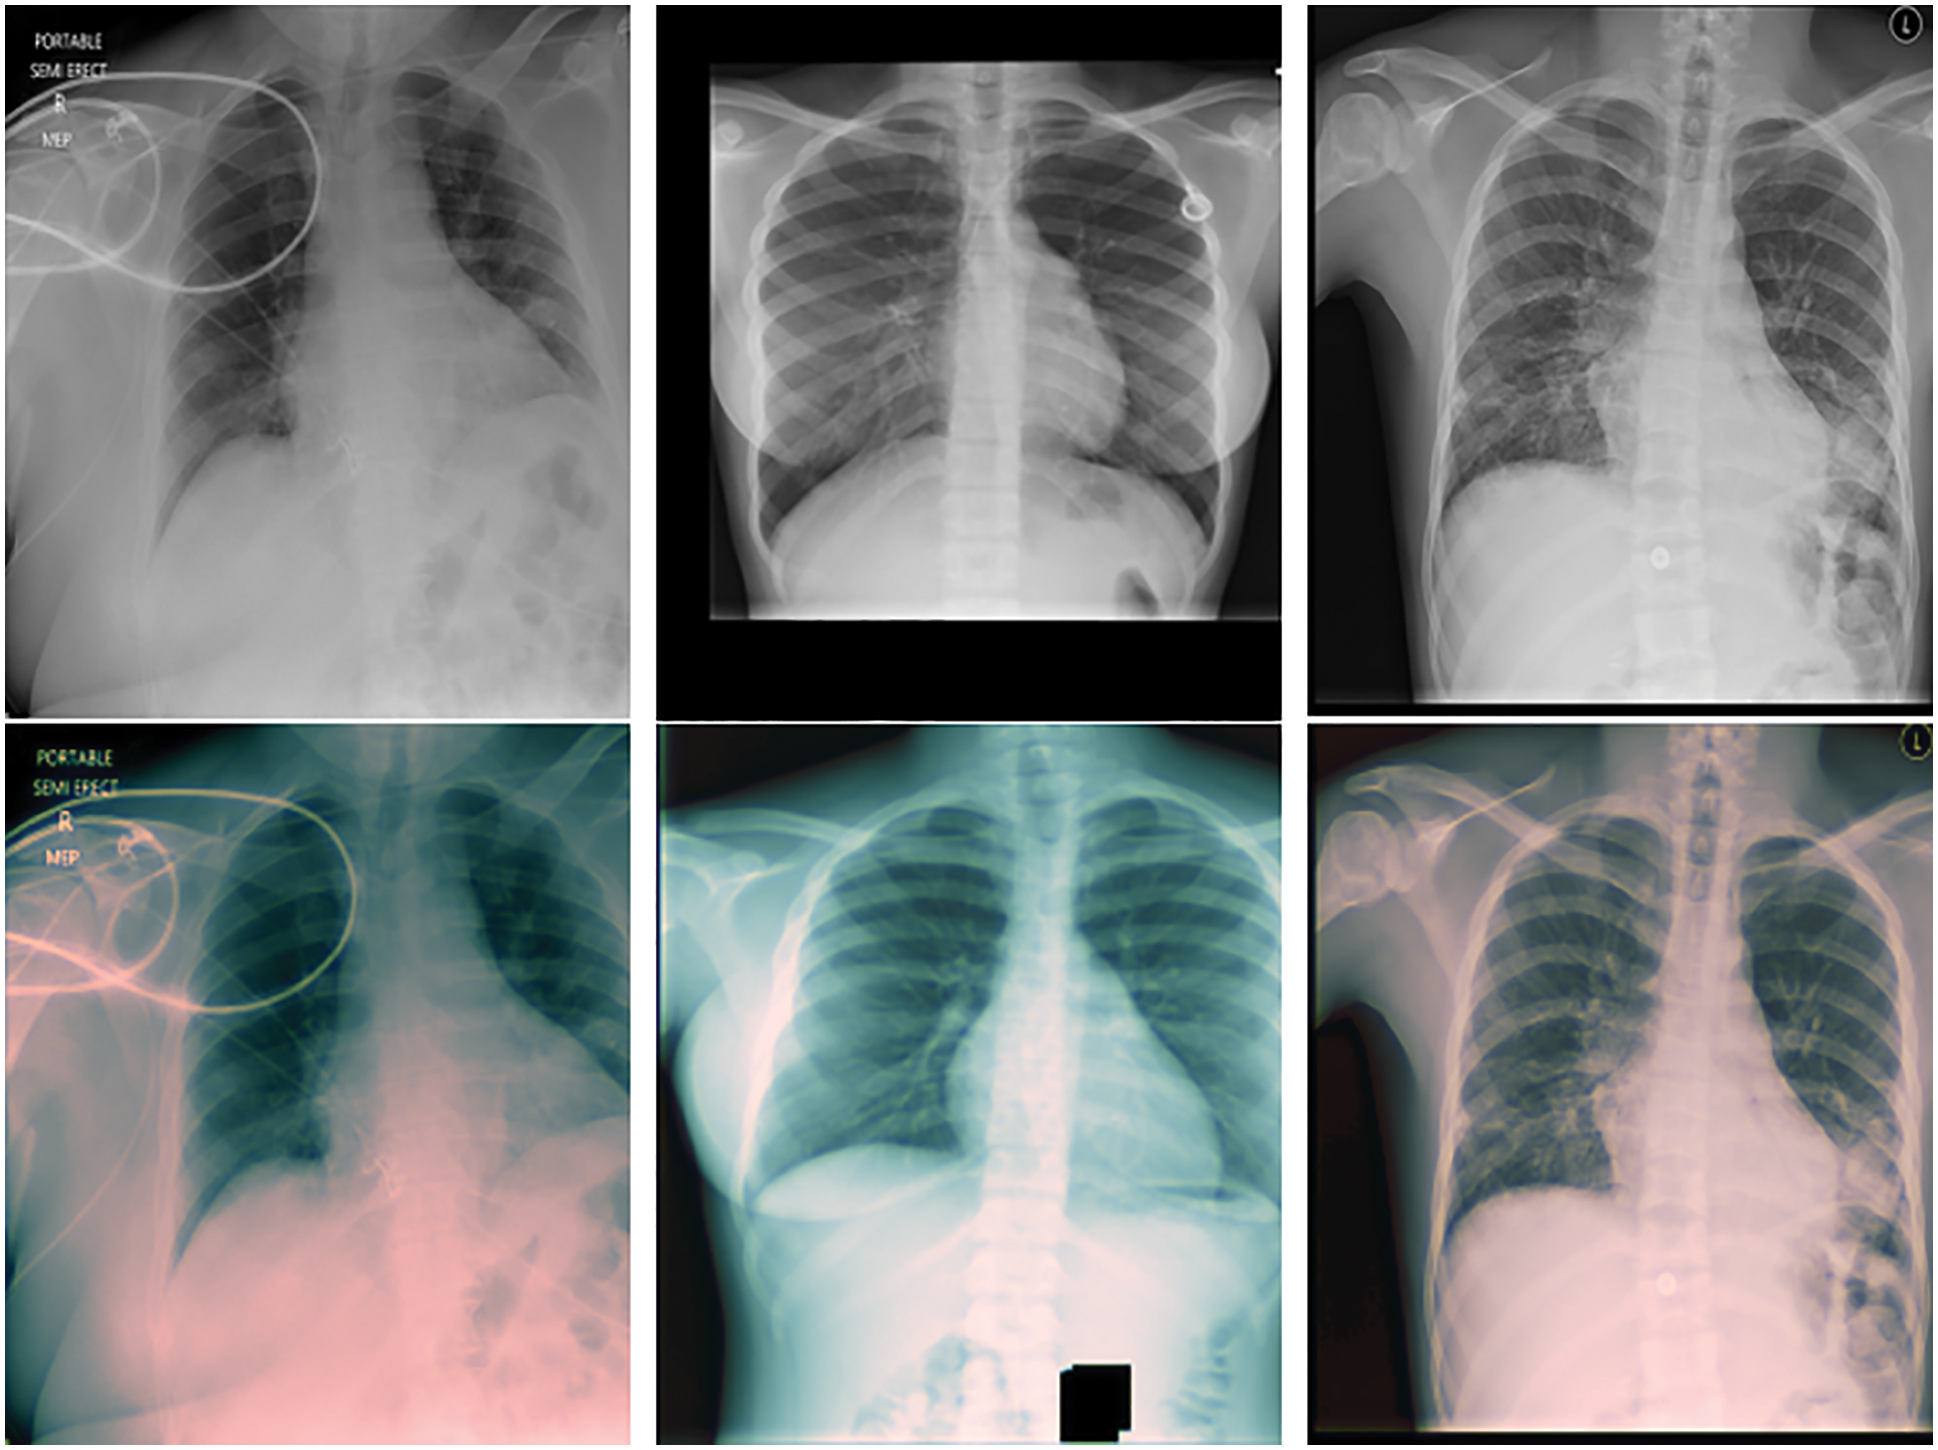

Precision, recall and F-measure are the main metrics to measure the performance of the classification algorithms. Precision shows how many of the values predicted as Positive are actually Positive. Recall is a metric that shows how many of the transactions that should have been predicted as Positive were predicted as Positive. F1 Score value shows the harmonic mean of the Precision and Recall values. In addition, the precision, recall and F1-score values are shown in Tab. 6. Since lung opacity is the hardest class to prediction, precision value was found to be lower than other data. Similarly, the F1 score is related to the precision value, so it is calculated lower than the other classes. Subsequently, the values of the confusion matrix are shown in Fig. 8 and the samples misdiagnosed by the ensemble model are shown in Fig. 9. According to the results, it can be said that the ensemble model is successful for three different classifications.

Figure 9: Samples misdiagnosed by the ensemble model for three classes

Finally, the values of the confusion matrix are shown in Fig. 10 and the samples misdiagnosed by the ensemble model are shown in Fig. 11. According to the results, it can be said that the ensemble model is successful for four different classifications. Diagnosis of the lung opacity class reduces the accuracy values to a bit at this stage, especially since it has similarities with Covid-19 and pneumonia types.

Figure 11: Samples misdiagnosed by the ensemble model for four classes